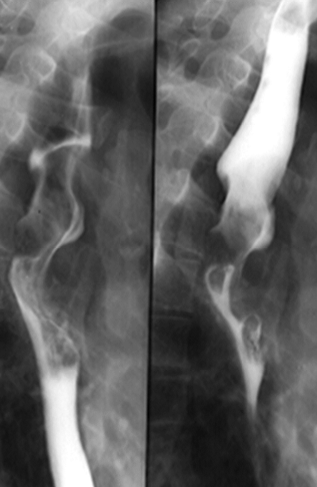

Diverticuli medioesofagieni

Diverticul medioesofagian